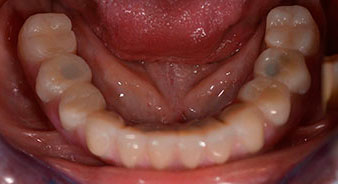

Um die Divergenz der distalen Implantate auszugleichen, werden abgewinkelte Abutments (35 Grad) eingeschraubt, sodass die Austrittsprofile sämtlicher Implantate möglichst senkrecht zur Kauebene stehen. Dies ist Voraussetzung, um die provisorische und später auch die endgültige Versorgung okklusal verschrauben zu können (Abb. 15 und 16).

Implantate

Abb. 15

Abb. 16